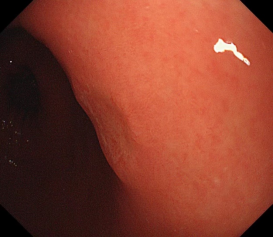

胃内粘膜下隆起,术前超声提示来源于固有肌层,术前判断需胃壁全层切除。

术中所见与术前判断相符,行内镜全层切除术EFTR,术后严密封闭创面,患者2日后安全出院,术后病理诊断胃间质瘤。